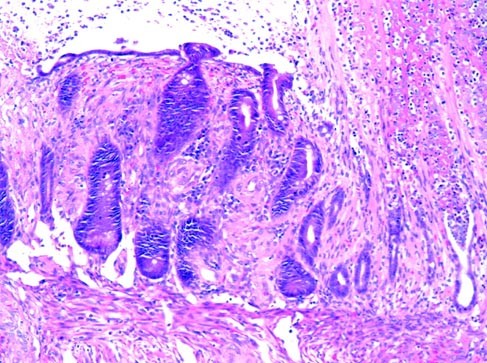

Histologic examination of each of the colonic resection specimens revealed a florid proliferation of small vascular channels arising adjacent to a chronic ulcer (Fig. 1A). The proliferation extended from the submucosa to the subserosal connective tissue. In four cases (Cases 1, 2, 4, and 5) the vessels extended into the mucosa. At low power, the lesions had a distinctly lobular architecture, similar to a pyogenic granuloma. This lobularity was accentuated on sections immunostained for CD31 (Fig. 1B). The vessels were lined by plump endothelial cells that showed strong expression of CD31 (Fig. 1, C–D). The lesions showed focal areas of increased cellularity with spindled cells (Fig. 2); however, the overall appearance was inconsistent with Kaposi’s sarcoma. The endothelial cells lacked significant hyperchromasia, and nuclear pleomorphism was slight. Mitotic figures were encountered infrequently; no atypical mitoses were observed.

Muscular fibroplasia was noted in the lamina propria adjacent to the lesions, suggesting mucosal prolapse. In two of the cases (Cases 1 and 5), ischemic-type changes were present in the surrounding mucosa, including regenerative epithelium with small, atrophic crypts and hyalinization of the lamina propria (Fig. 3). A possible arteriovenous malformation (Fig. 4) was identified in two cases (Cases 3 and 5). There were no changes to suggest chronic inflammatory bowel disease, and no infectious agents were identified. A Warthin-Starry stain performed on Case 4 revealed no organisms, excluding bacillary angiomatosis.